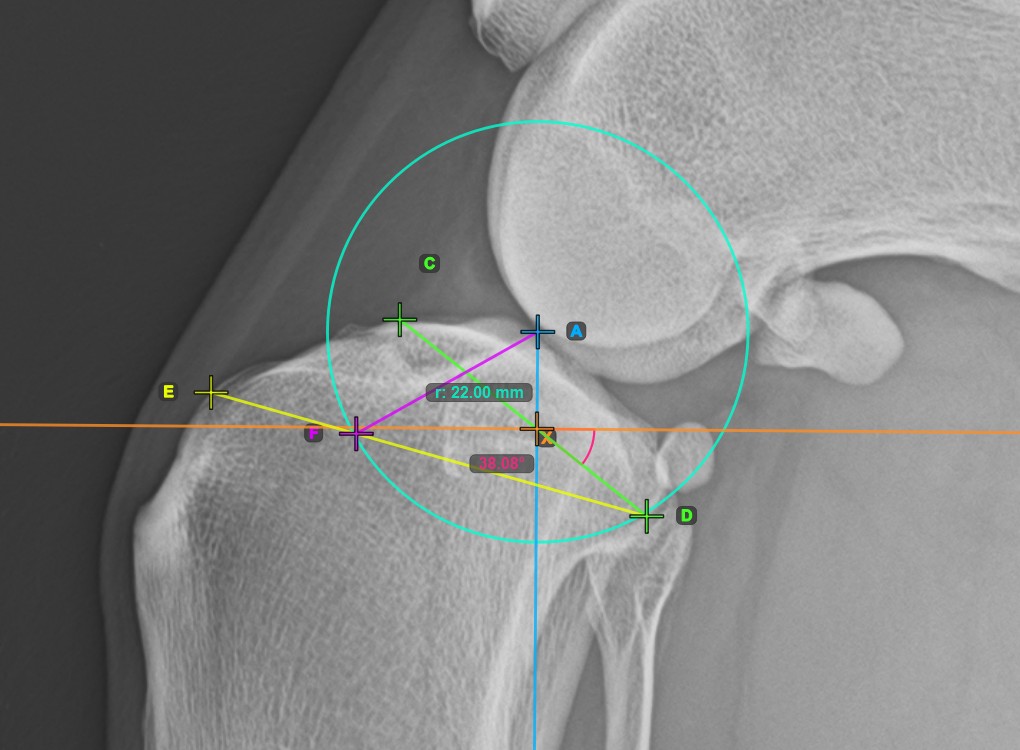

Start the TPLO extension by marking the tibial crest. The sawblade size for the TPLO extension is automatically calculated as the distance between the Eminentia Intercondylaris and the point located two thirds along the line connecting the most caudal point of the tibial head and the tibial crest.

The image below depicts the usual placement of the tibial crest point on the tibial head.

Before completing the TPLO extension, users can modify the parameters of the measurement required to calculate the rotation distance for the procedure in the advanced measurement mode toolbar.

• Fix the TPA Angle calculation by toggling the Fix checkbox. Any modification to the TPA Angle will otherwise be reflected in the rotation distance calculation.

• Enter the desired TPA Angle of the TPLO procedure in the Desired TPA (°) input field.

• To recalculate the sawblade size, enter the desired value in the Sawblade Size input field.

Press Calculate rotation distance to perform the required calculations for the TPLO procedure. The calculated rotation distance will be shown in the advanced measurement mode toolbar.